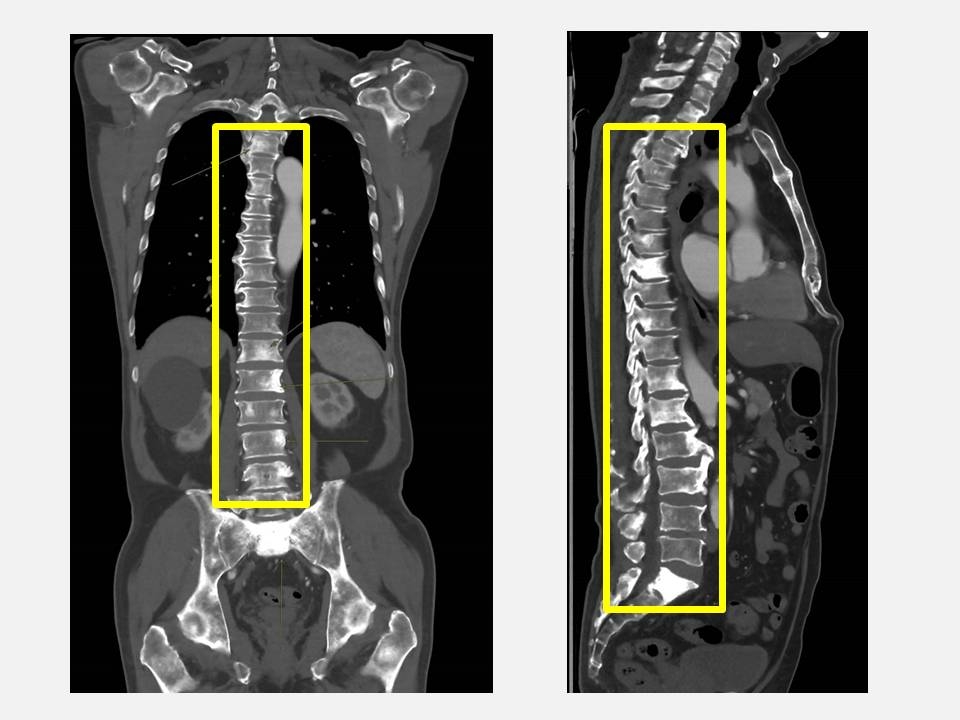

【前列腺癌/排尿/問題/症狀/確診/檢測】台灣仁愛長庚合作聯盟醫院在Facebook發文,分享一宗病例,指有一名70歲的余先生近月因背痛嚴重影響生活品質,以為只是年紀大造成的脊椎退化或筋骨痠痛,靠止痛藥和熱敷就能緩解,因此沒有積極就醫。

他因子女堅持才參加醫院的例行健康檢查,結果意外發現前列腺特異抗原(PSA)與鹼性磷酸酶(ALK-P)指數明顯異常,醫生察覺可能是罹患前列腺癌且轉移,立即安排影像學檢查與轉介至泌尿科門診,進一步檢查後確診為前列腺癌合併瀰漫性骨轉移,幸透過跨科合作及早確認病因,余男已展開治療,目前病情獲得控制。

早期前列腺癌沒明顯症狀泌尿科主任劉緯陽表示,早期前列腺癌通常沒有明顯症狀,許多患者常因排尿困難、夜尿頻繁、血尿,甚至像余男一樣出現骨痛才就醫,往往病情已屬末期。余男因背痛接受體檢而發現異常,算是「因禍得福」,否則若再拖延,可能導致骨折、神經壓迫等嚴重併發症。